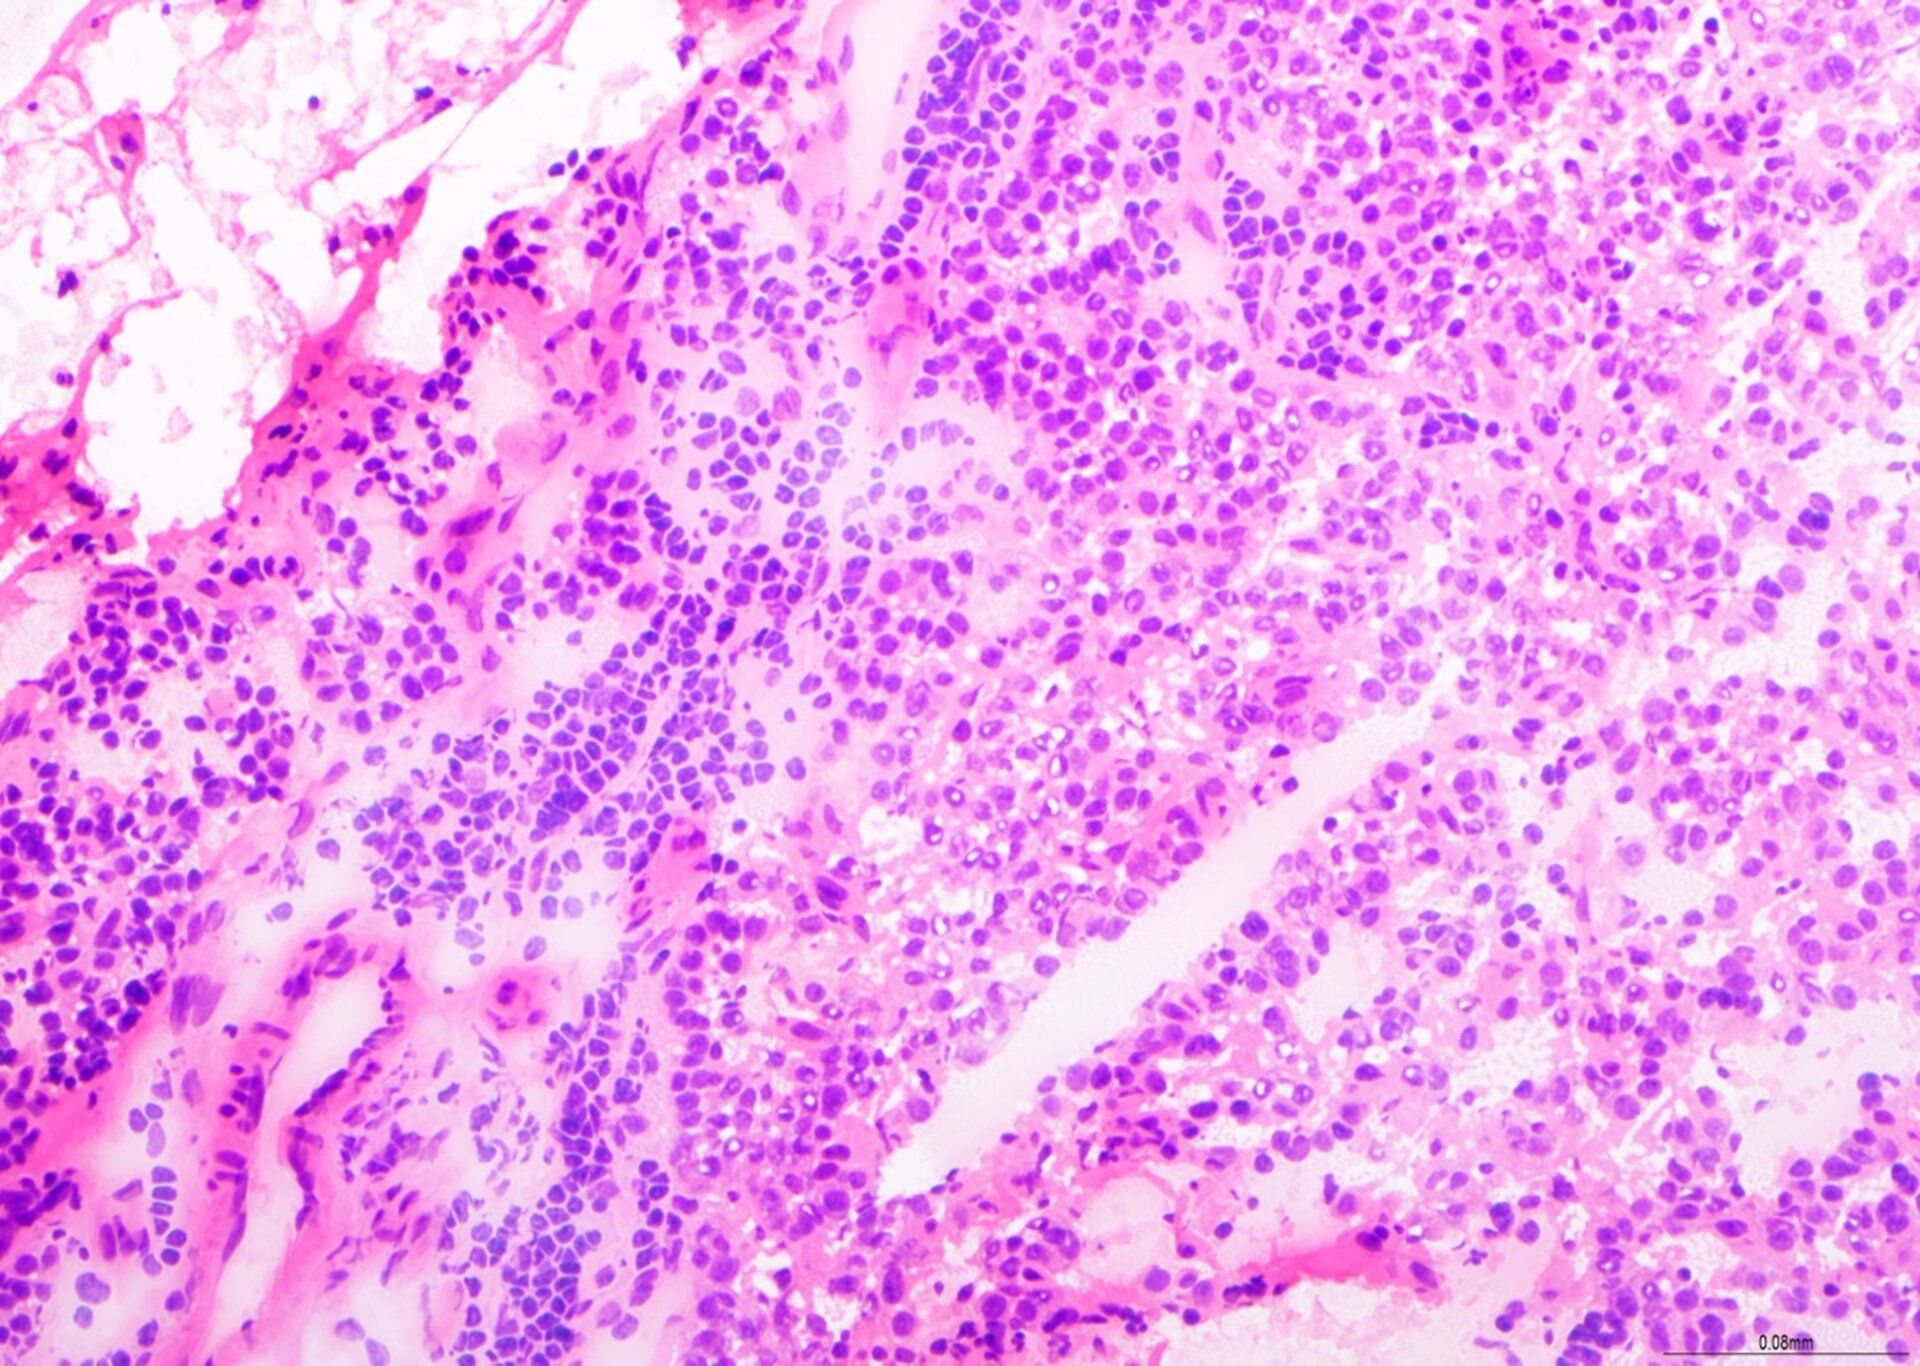

H&E - Esquema BMT

Esta é uma excelente preparação para biópsia de TMO, com coloração H&E balanceada, bons detalhes de cromatina e coloração seletiva de tipos celulares no tecido da medula óssea. Esta lâmina recebeu pontuação 9/10 na avaliação.